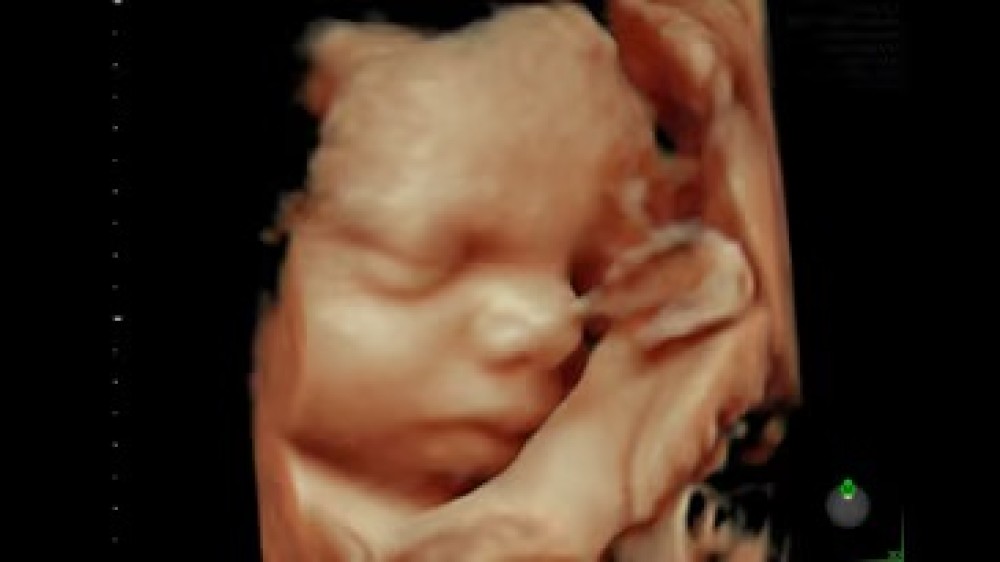

Voluson E6 GE Healthcare-in orta-yüksək səviyyəli ultrasəs cihazıdır və əsasən qadın sağlamlığı, obstetrik və ginekoloji müayinələr üçün nəzərdə tutulub. Sistem Radiance System Architecture üzərində qurulub və bu, yüksək keyfiyyətli 2D və 3D/4D görüntüləmə, həmçinin Color Doppler funksiyasını təmin edir.

Voluson E6-in avtomatlaşdırılmış funksiyalarıergonomik dizaynı operatora iş axınını optimallaşdırmaq, müayinələri daha sürətli və səmərəli icra etmək imkanı verir. Sistem fetal inkişafın, plasentanın, ürək fəaliyyətinin və qadın reproduktiv sisteminin dəqiq qiymətləndirilməsi üçün nəzərdə tutulmuşdur, eyni zamanda gündəlik klinik iş yükünü asanlaşdırır.